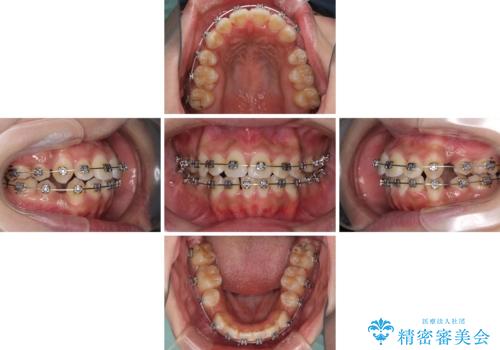

- メタルブラケット

- 2年1ヶ月

上下前歯部叢生のスペース獲得のため、上下顎左右小臼歯各1歯(計4本)と全ての親知らずを抜歯して、矯正治療を行うこととしました。

上下の正中位置が大きくずれていたため、治療期間の長期化や正中が合わないまま終了することが予想されましたが、思っていた以上にスムーズに歯が移動し、満足いただける仕上がりとなりました。